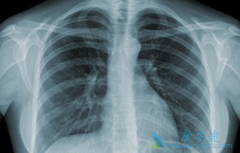

派姆单抗/K药的加入能够提升肺癌化疗的疗效吗?

今年可以说是基因免疫疗法呈爆发式增长的一年,越来越多的基因免疫药物开始出现。成为了继手术,放化疗,抗癌靶向药物以外的新型癌症治疗方式。 派姆单抗 是我们最常使用的一款基因免疫药物,治疗靶点非常之多,而且往往效果非常之好。那么如果将派姆单 ...